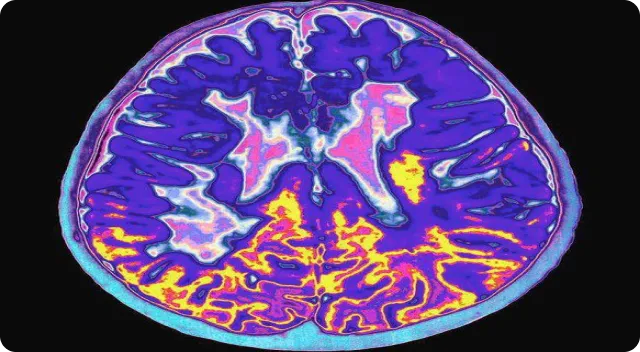

Multiple Sclerosis (MS) is a chronic neurological condition characterized by immune-mediated inflammation affecting the central nervous system. Regenerative medicine explores MSCs and exosomes therapy as supportive biological approaches to assist immune balance and regulate inflammatory pathways.

Multiple Sclerosis (MS) is a chronic neurological condition characterized by immune-mediated inflammation that affects the protective covering of nerve fibers within the central nervous system. The condition can influence mobility, coordination, sensory perception, and overall neurological function in varying degrees from person to person. In regenerative medicine, umbilical cord–derived mesenchymal stem cells (MSCs), often combined with exosomes therapy, are increasingly explored as supportive biological approaches aimed at assisting immune balance, regulating inflammatory pathways, and encouraging cellular communication under medical supervision.

Multiple Sclerosis involves immune-related activity that influences nerve signaling efficiency within the brain and spinal cord. Symptoms and progression patterns vary widely and may include fatigue, muscle weakness, coordination differences, and sensory changes. Because each individual experiences MS differently, multidisciplinary management approaches are commonly recommended to support long-term neurological function and quality of life.